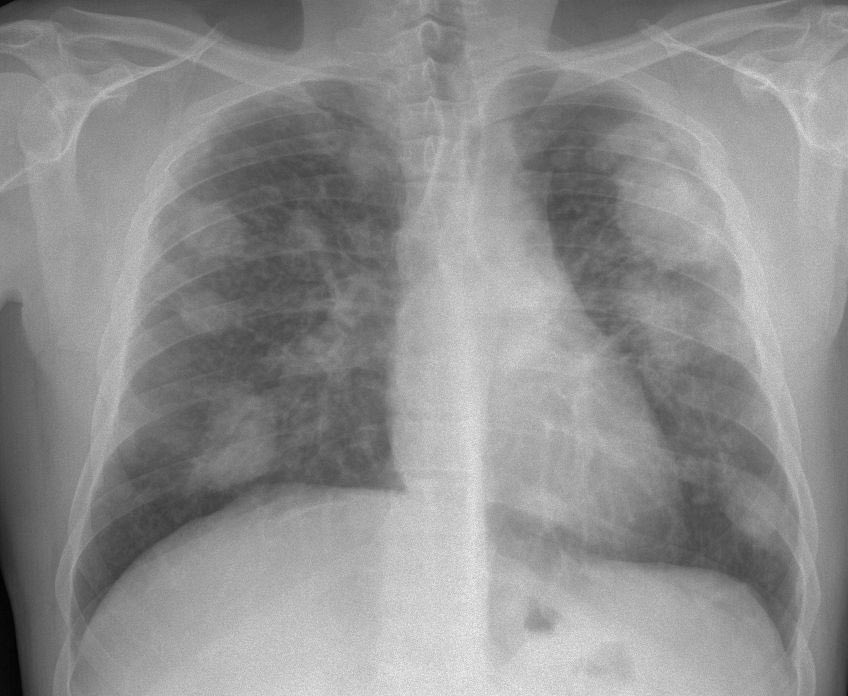

👈تصل إلى داخل رئة الإنسان عند استنشاقها ما يؤدي إلى الإصابة بالتهابات رئوية

📍استنشاق #الغبار المحتوي على مركبات#السيليكا الدقيقة وعلى مدار سنوات عديدة، يؤدي للاصابة بمرض

#السحار

👈وأعراضه تشمل:

نقص التنفس✅

التعب ونقصان الشهية✅

كحة جافة✅